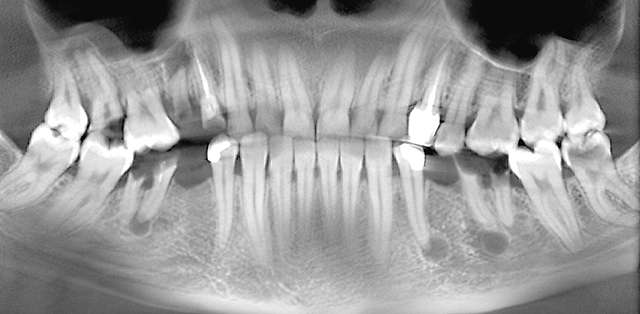

Surgical guides are used for more safety and precision in complex cases that require dental implant therapy. Guides are 3D printed based on the digital planning of the surgery, using specialised software and the CBCT of the patient.

For optimal esthetic results, the final design must always be the refference for the surgery. This design together with the CBCT of the patient are compiled to find the ideal position of the dental implants.